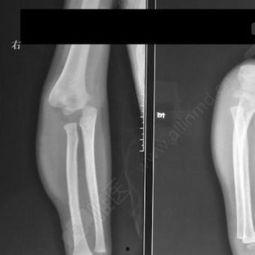

1. 观察肘关节情况:首先,仔细观察孩子的肘关节,确定是否真的发生了脱位。

4. 检查复位效果:复位后,再次观察肘关节,确认是否已经恢复到正常位置。